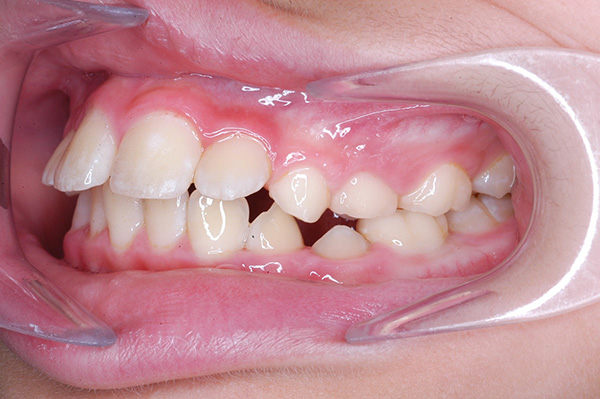

| 主訴 | 上顎犬歯の位置異常 | 診断名 | 上顎左右側犬歯埋伏歯症 | ||||

| 顔貌所見 | 正貌はほぼ左右対称。側貌はconvex type、口唇閉鎖不全、口元の突出感が認められた。 |

| 口腔内所見 | over jet 5.5mm,over bite 5.0mm,大臼歯関係はⅠ級 、Hellmanのdental ageはⅢBであり上突歯列を呈していた。 |

| セファロ所見 | Sellaに対して下顎頭は後方位だが下顎骨は大きくしっかりとした形態をしており前後的にはⅠ級、垂直的にはロウアングルの骨格形態をしていた。 上顎前歯は唇側傾斜を呈していた。 |

| パノラマ所見 | 上顎左右側犬歯は近心傾斜し側切歯歯根に重なるように認められた。 |